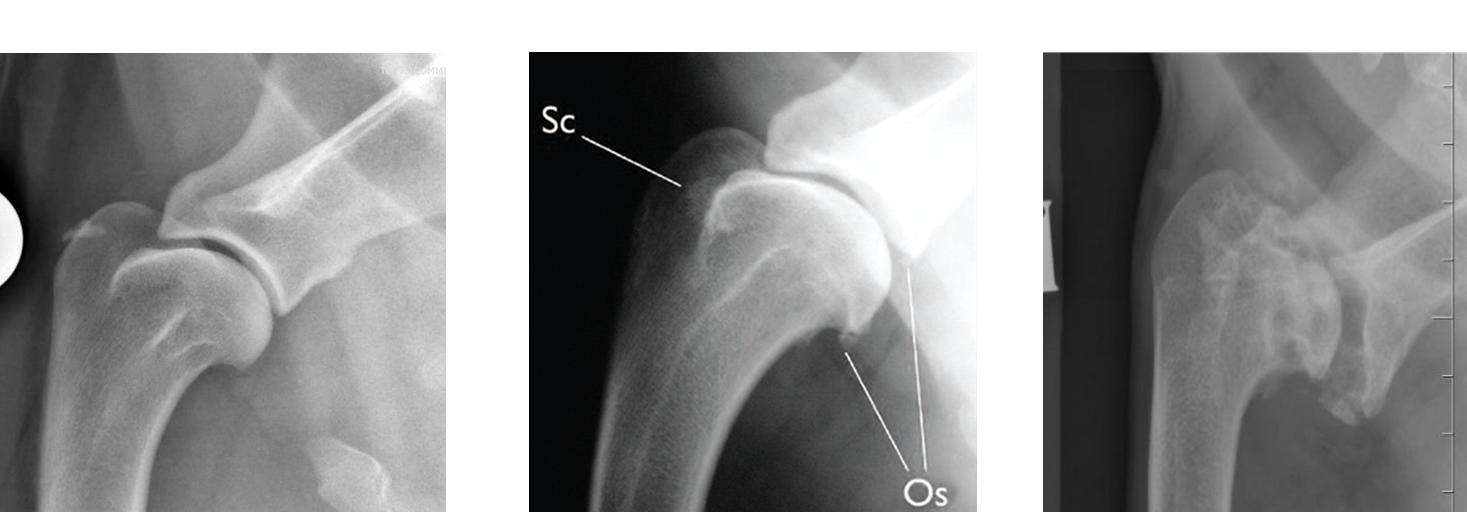

What will be seen in chronic shoulder arthrosis?

Lots of new bone (osteophytes)

Underlying cause often not evident

label the normal

sclerosis and osteophytes

sclerosis, uneven joint space, osteophytes (New bone)

WHAT do we expect to see at normal joint

nicely rounded and smooth margin to the

head of the humerus and look at the margins of

the distal part of the scapula spine and the joint

space here.

So nice and smooth and nice.